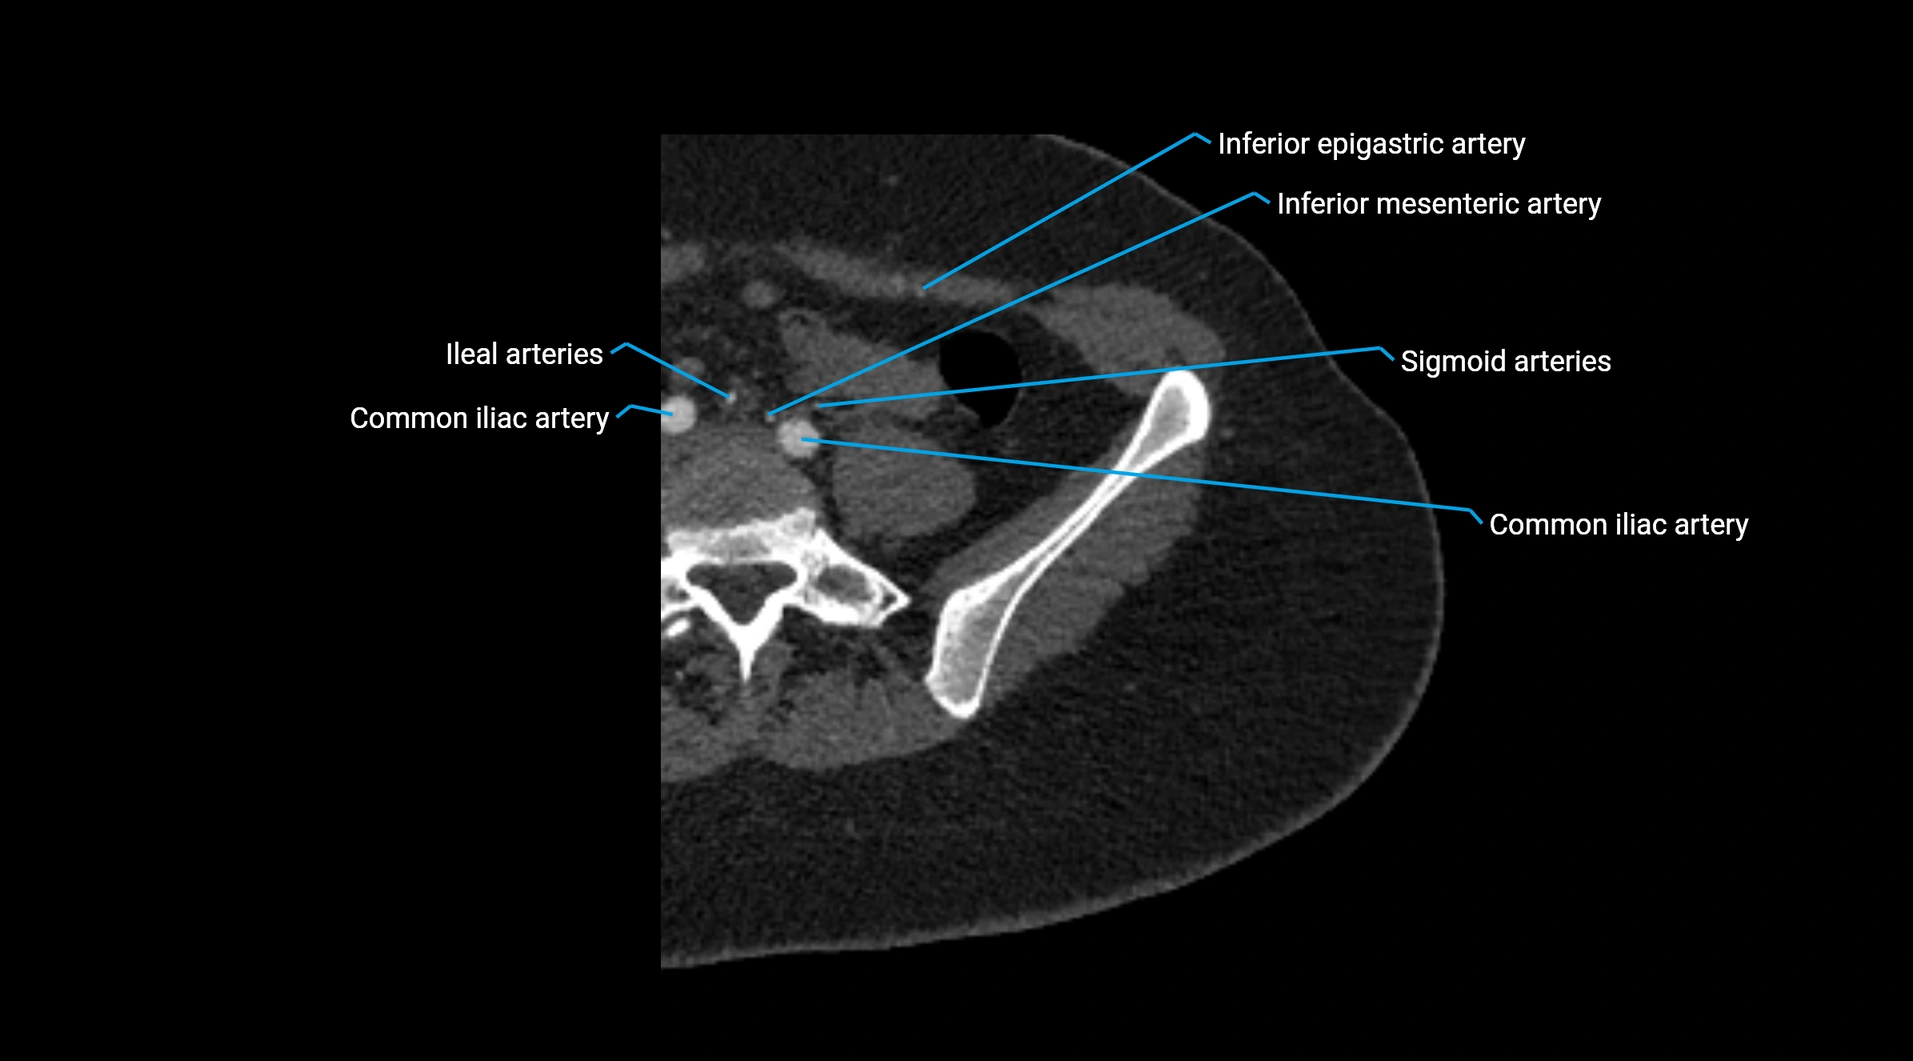

CT images

image

Contrast-enhanced CT (CTA):

• Gold standard for abdominal aortic imaging

• Provides excellent detail of lumen, wall, aneurysm, thrombus, and branch vessels

• Multiplanar and 3D reconstructions help in aneurysm measurement, stent graft planning, and dissection evaluation

• Terminal branches: right and left common iliac arteries

• Unpaired visceral branches: celiac trunk, superior mesenteric artery (SMA), inferior mesenteric artery (IMA)